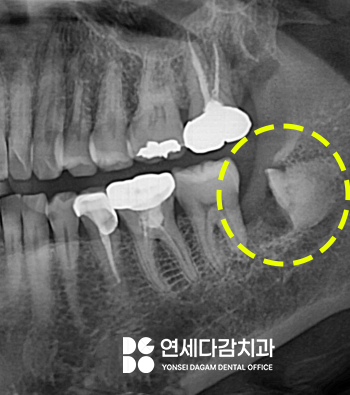

또 다른 케이스인데요.

이곳도 마찬가지로

오금역 치과 에서 앞서 보여드렸던

것과 같은 상황이었습니다.

이곳 또한 수평으로

매복되어 부분 맹출 된

상태로 잇몸 염증 및 통증을 일으키고 있었죠.

이 부위만 마취하에

잇몸을 절개하고 치아의

머리 부분인 치관만 조심스럽게 절단합니다.

치근만 남겨둔 상태로

봉합하여 치유되면

말끔한 잇몸으로 돌아오는데요.

세균이 들어올 공간이 사라지면서

뿌리는 안전하게 뼈 속에

묻어두게 됩니다.